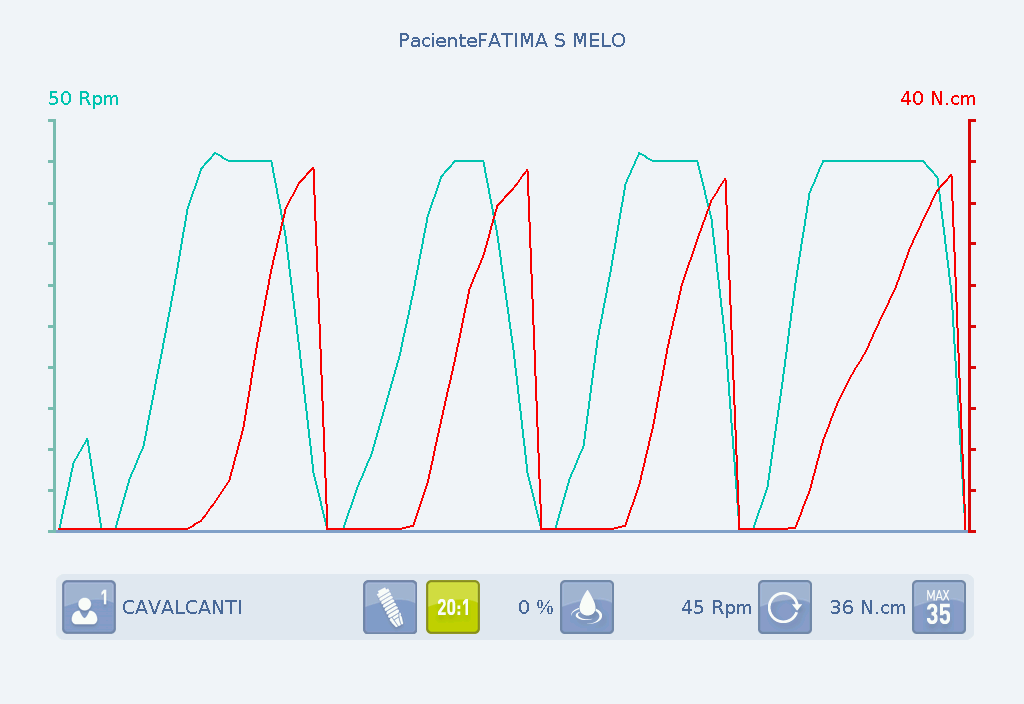

Alguns motores permitem medir tanto o torque utilizado sobre as brocas para o preparo do leito cirúrgico (osteotomia), bem como o torque de instalação, dando total controle da força empregada na broca e na inserção do implante, além da velocidade aplicada.

Gráfico B: Velocidade e torque empregados para instalar um implante Maestro 3.5 por 11 mm na região de primeiro pré-molar superior esquerdo.